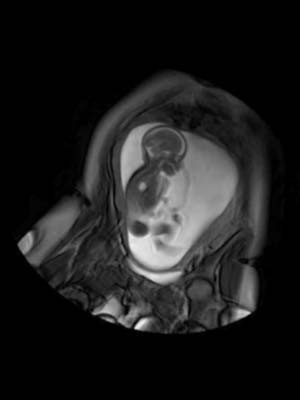

Cientistas britânicos deram início a um projeto de seis anos para mapear as conexões nervosas desenvolvidas no cérebro de um bebê ainda no útero e imediatamente após o nascimento. Assista à reportagem em vídeo (desabilite o bloqueador de pop-ups, caso necessário).

No momento em que um bebê respira pela primeira vez, muitas das principais ligações no cérebro já estarão feitas.

Pesquisadores do Guy"s and St Thomas" Hospital, do King"s College de Londres, do Imperial College e da Universidade de Oxford querem produzir um diagrama que mostre como o cérebro cresce, a um nível de detalhe que dizem ter sido impossível de se obter até agora.

Imagens do cérebro são cortesia do Centre for the Developing Brain, do King"s College de Londres.